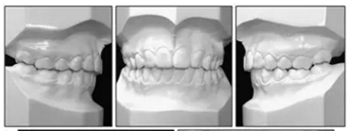

治療的總體目標得以實現(xiàn)(圖8)??傊委煏r間為36個月。面部方面表現(xiàn)出充分的唇閉合和愉快的微笑。切牙運動后有一些唇縮回。覆蓋和覆合良好,并且上下牙弓相協(xié)調(diào)(圖9)。I類磨牙關(guān)系得以實現(xiàn)。左側(cè)后牙反合得以矯正。下頜第二磨牙成功直立。